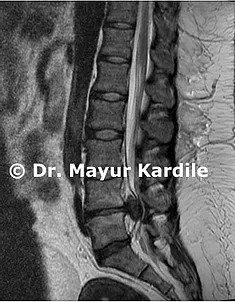

• Doctor's Examination: History and thorough physical examination to identify the herniated disc • X-ray: To assess spinal alignment and rule out fractures • CT-Scan: For detailed bony anatomy • MRI Scan: Most accurate test to diagnose herniated disc — shows the disc, nerve compression, and surrounding structures